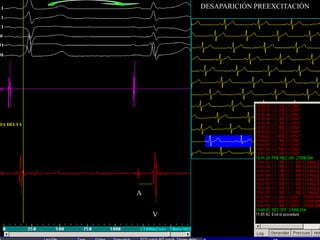

DESAPARICIÓN PREEXCITACIÓN

DA DELTA

A

V